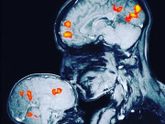

Как же быстро растет малышка, каждый день что то новое) от ее громких«бла бла бла блааа» иногда голова побаливает))))) если хоть немного в тетю пойдет, точно будет болтушкой)ночью переворачивается на бочок ко мне, любит носиком уткнуться и спать, а утром … Читать далее